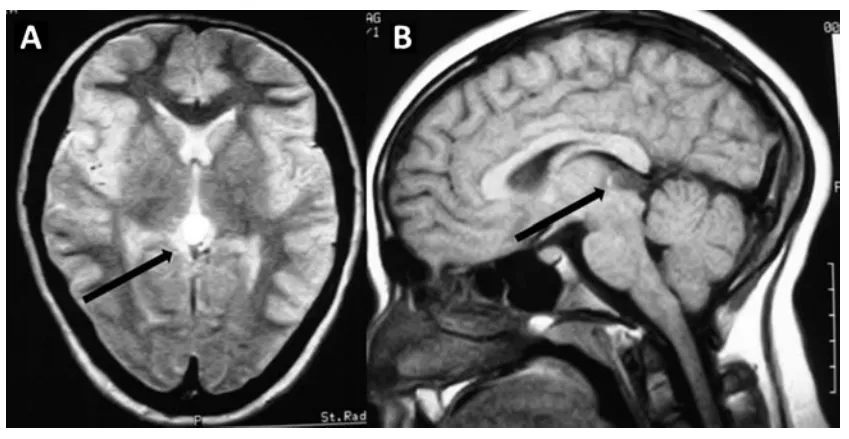

六岁的鑫鑫,因在幼儿园意外摔伤头皮就诊,CT检查意外捕捉到松果体区阴影与局部钙化灶;进一步MRI精查,一枚221417mm的占位病变随之浮出水面。 三十六岁的晴晴,不过是因鼻炎顺带行颅脑...